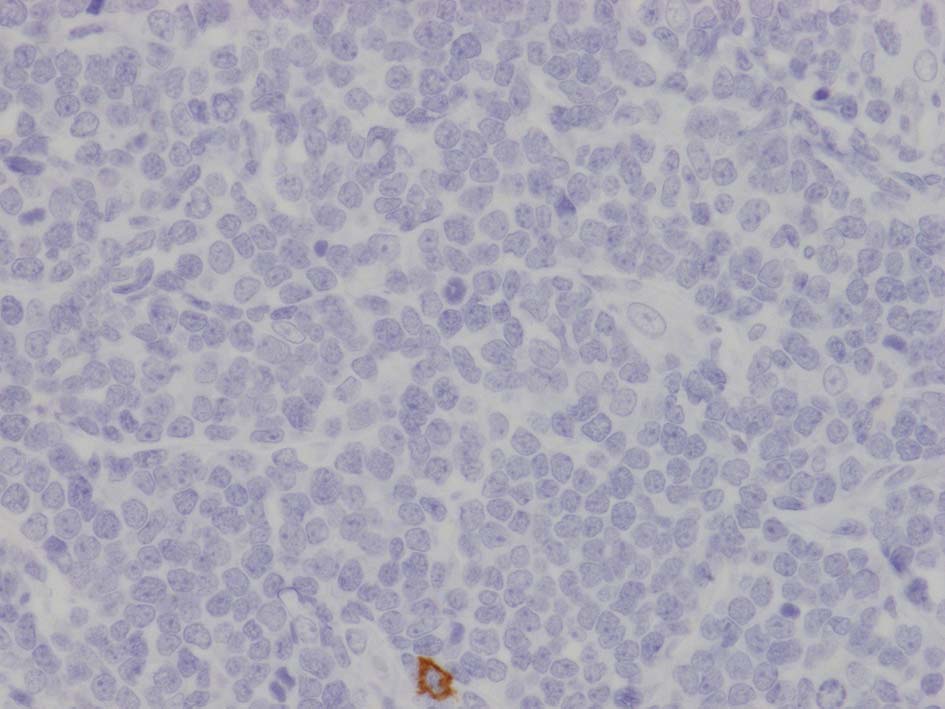

loupe像Aの領域: 精細管をスペアするように, 小型リンパ球優位, 一部中型のlymphoid cellsがシート状密に浸潤増殖する. tubulesのほとんどにはlymphoid cellsが浸潤していないが, LELに似たようなlympho-tubular lesionが少数認められた. x400高倍率では, 増殖細胞は, 粗く, 凝集したクロマチンをもつ類円形, non-cleavedな核をもつ細胞質の乏しいlymphoid cellsである. 核小体か凝集したクロマチンかわかりにくい.

左肘窩リンパ節は正常構造を消失. 類円形の繊細なクロマチンをもつ,核小体の明瞭な核をもつN/C比大の細胞が密に増殖している. 精巣の成熟したリンパ球とは核所見が異なる(白膜増殖部には類似の細胞が認められていた).

FCMでTdT陽性細胞が多数. 免疫染色ではCD3+, CD4+, CD8+, BCL2+. TdT+, CD99(MIC2)+, CD34-, CD117(c-KIT)-であった.

左肘窩リンパ節の病理診断は T-lymphoblastic lymphoma(T-LBL)になる. 1年後の再発で, 精巣リンパ腫と異なったものが発症するとは考えにくく, 精巣病変にTdT, CD99, CD34, CD117を追加染色した.